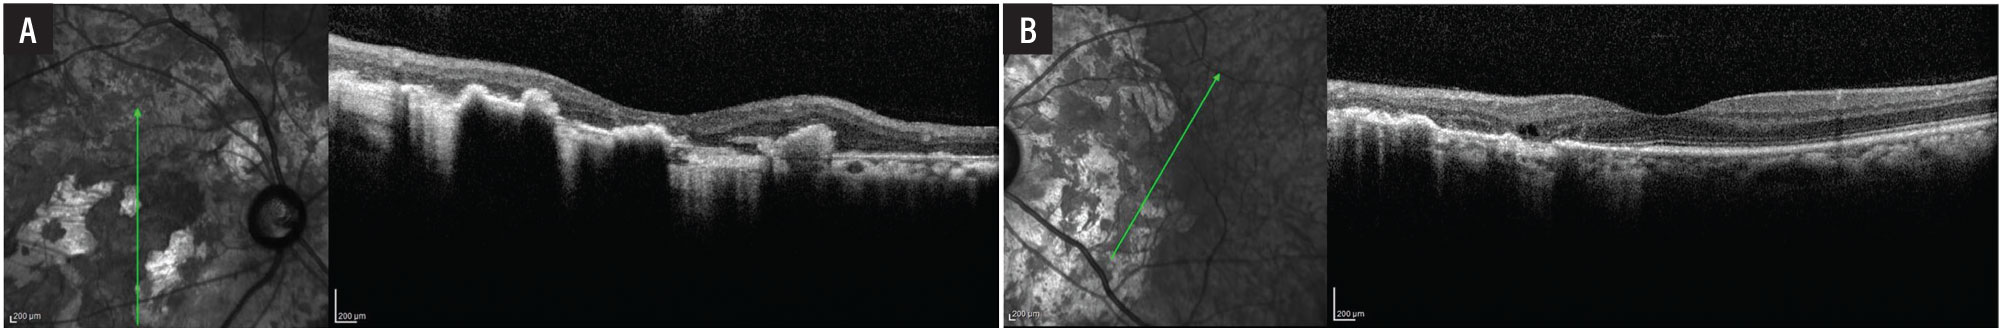

Fundus examination of the right eye (Figure 1A) demonstrated clear vitreous without vitritis. The optic nerve was flat with sharp margins. Circumpapillary and contiguous to the disc, there was a large helicoid area of chorioretinal atrophy with intermixed hyperpigmentation involving the entire macula. The vessels were of normal course and caliber without sheathing and the periphery was unremarkable.

Fundus examination of the left eye (Figure 1B) also demonstrated clear vitreous without vitritis. The optic nerve head was flat with sharp margins. Circumpapillary and contiguous to the disc was a helicoid area of chorioretinal atrophy, smaller than the right eye, with intermixed hyperpigmentation abutting, but not involving, the fovea.

The left eye also showed an area of hypopigmentation along the inferior arcade at the edge of chorioretinal atrophy in the left eye. The vessels were of normal course and caliber without sheathing and the periphery was unremarkable.

Figure 1. Pseudocolor fundus imaging demonstrates bilateral helicoid chorioretinal atrophy emanating from the disc. |

Optical coherence tomography of the macula showed preserved inner retinal laminations with large areas of outer retinal atrophy and retinal pigment epithelium migration the right eye (Figure 2A) and outer retinal atrophy in the nasal macula with preserved inner and outer retinal lamination subfoveally and in the temporal macula in the left eye (Figure 2B).

Figure 2. A) Optical coherence tomography shows marked outer retinal atrophy involving the entire macula in the right eye. B) The fovea and temporal macula in the left eye are spared. |